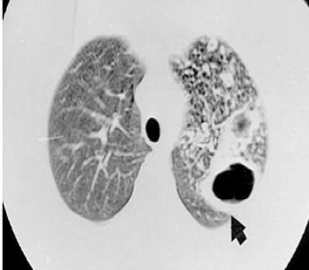

Como identificar a tuberculose no raio-x?

O diagnóstico por imagem é iniciado por avaliação do Raio-X, que deve ser solicitado para todo paciente com suspeita clínica de Tuberculose Pulmonar após a anamnese e exame físico. Essa solicitação tem por objetivo fazer a exclusão de outros diagnósticos diferenciais, avaliar a extensão do acometimento da doença e acompanhar a evolução do tratamento. Alguns achados suspeitos de no Raio-X são as cavidades, nódulos, consolidações, massas, derrame pleural e alargamento do mediastino.